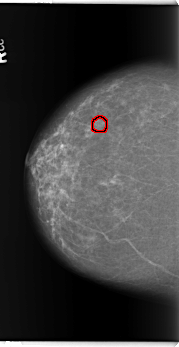

ics_version 1.0 filename B-3362-1 DATE_OF_STUDY 14 8 1997 PATIENT_AGE 77 FILM FILM_TYPE REGULAR DENSITY 2 DATE_DIGITIZED 4 6 1998 DIGITIZER LUMISYS LASER SEQUENCE LEFT_CC LINES 5936 PIXELS_PER_LINE 3304 BITS_PER_PIXEL 12 RESOLUTION 50 NON_OVERLAY LEFT_MLO LINES 5888 PIXELS_PER_LINE 3528 BITS_PER_PIXEL 12 RESOLUTION 50 NON_OVERLAY RIGHT_CC LINES 5896 PIXELS_PER_LINE 3040 BITS_PER_PIXEL 12 RESOLUTION 50 OVERLAY RIGHT_MLO LINES 5896 PIXELS_PER_LINE 3312 BITS_PER_PIXEL 12 RESOLUTION 50 OVERLAY |

FILE: B_3362_1.RIGHT_CC.OVERLAY TOTAL_ABNORMALITIES 1 ABNORMALITY 1 LESION_TYPE CALCIFICATION TYPE ROUND_AND_REGULAR DISTRIBUTION CLUSTERED LESION_TYPE MASS SHAPE IRREGULAR MARGINS MICROLOBULATED-ILL_DEFINED ASSESSMENT 3 SUBTLETY 3 PATHOLOGY BENIGN TOTAL_OUTLINES 1 BOUNDARY |